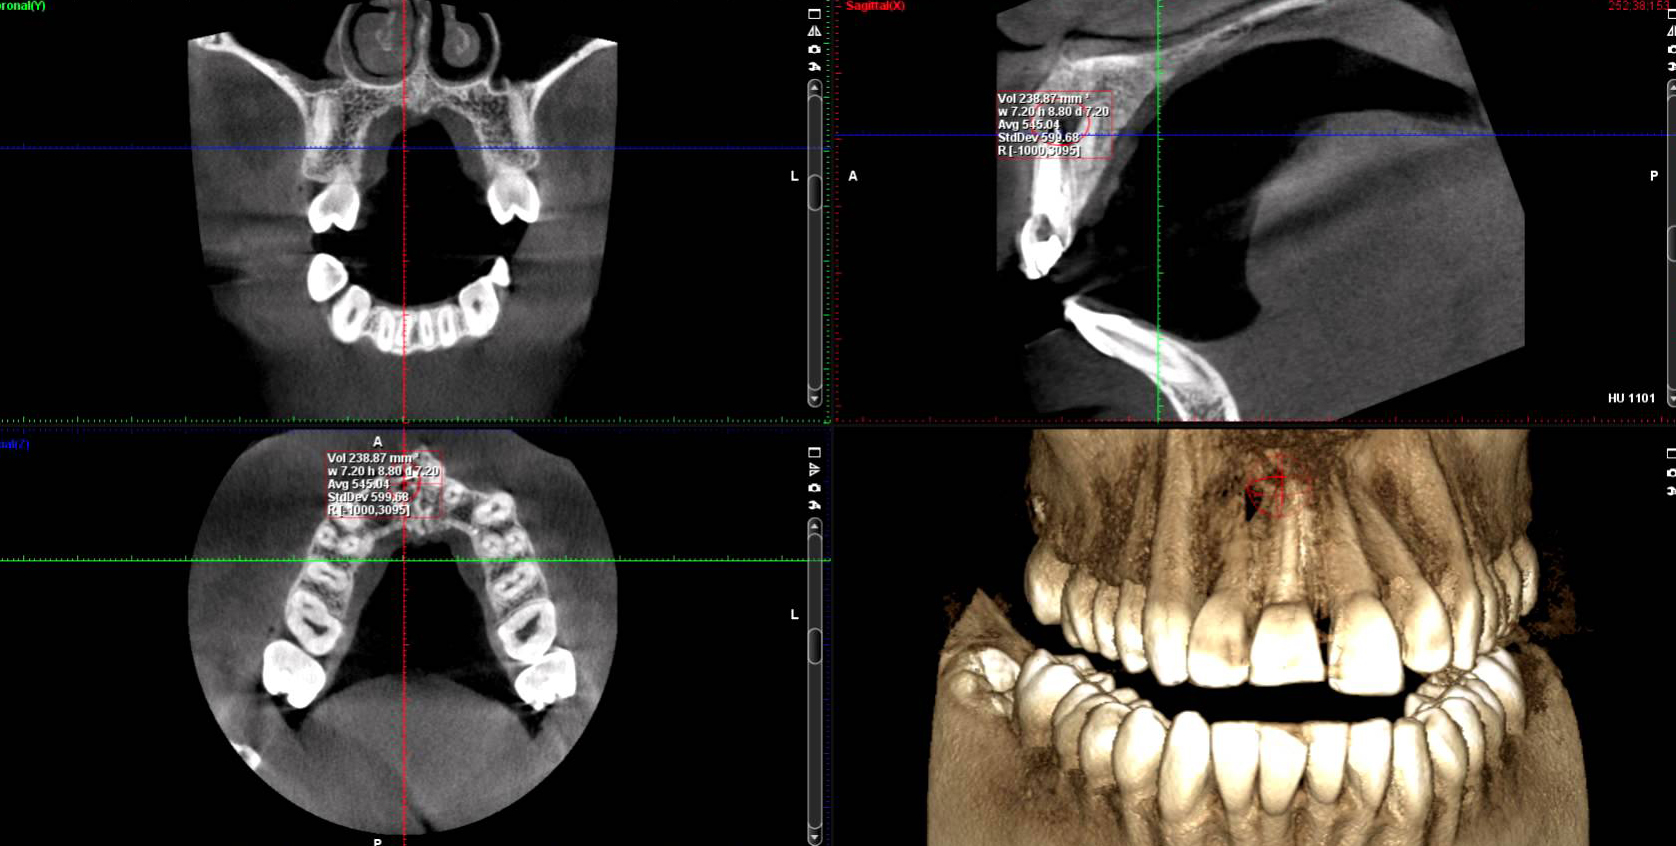

Cone Beam CT Interpretation American Association of Endodontists Digital Imaging In Endodontics Apart from the apex locators and endodontic electric motors, the usage of microscopes, digital radiography, cbct,. Cone beam computed tomography or cone beam volumetric tomography. The first part deals with the applications of the novel radiographic techniques in endodontics, mostly with the use of cbct. This review provides an overview of digital radiography as it exists, including advanced imaging such. Digital Imaging In Endodontics.

3D Imaging and Endodontics Cavendish Imaging Digital Imaging In Endodontics Apart from the apex locators and endodontic electric motors, the usage of microscopes, digital radiography, cbct,. This review provides an overview of digital radiography as it exists, including advanced imaging such as computed tomography (ct),. Cone beam computed tomography or cone beam volumetric tomography. This review provides an overview of digital radiography as it exists, including advanced imaging such as. Digital Imaging In Endodontics.

3D Imaging (CBCT) Compassion Endodontics Digital Imaging In Endodontics This review provides an overview of digital radiography as it exists, including advanced imaging such as computed tomography (ct),. Cone beam computed tomography or cone beam volumetric tomography. This review provides an overview of digital radiography as it exists, including advanced imaging such as computed tomography (ct),. This review provides an overview of digital radiography as it exists, including advanced. Digital Imaging In Endodontics.

CBCT and Endodontics Cavendish Imaging Digital Imaging In Endodontics Apart from the apex locators and endodontic electric motors, the usage of microscopes, digital radiography, cbct,. This review provides an overview of digital radiography as it exists, including advanced imaging such as computed tomography (ct),. This review provides an overview of digital radiography as it exists, including advanced imaging such as computed tomography (ct),. Digital radiography offers the benefit of. Digital Imaging In Endodontics.

3D Imaging in Endodontics Dent13 Digital Imaging In Endodontics The first part deals with the applications of the novel radiographic techniques in endodontics, mostly with the use of cbct. Apart from the apex locators and endodontic electric motors, the usage of microscopes, digital radiography, cbct,. Cone beam computed tomography or cone beam volumetric tomography. This review provides an overview of digital radiography as it exists, including advanced imaging such. Digital Imaging In Endodontics.